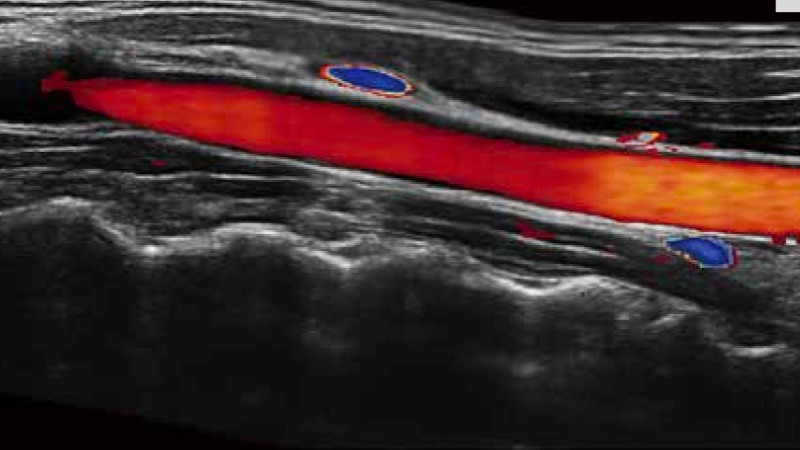

复合材料线阵探头

凭借狗万官方网站先进的成像技术和优异的探头技术提供的清晰的图像表现,您可以更自信地做出临床决策。